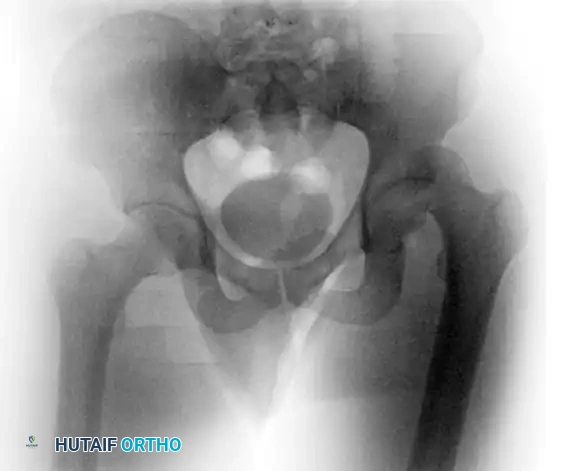

Radiographic Confirmation

An AP pelvis radiograph is obtained immediately to confirm concentric reduction. However, plain radiographs are notoriously insensitive for detecting small intra-articular osteochondral fragments or subtle joint incongruity.

FIGURE 55-54 Incongruous joint after closed reduction due to intraarticular fragments. A, Pre-reduction radiograph. B, Radiograph after reduction. Axial (C) and coronal (D) CT scans after reduction.

FIGURE 55-54 A: Pre-reduction radiograph of a posterior dislocation.

FIGURE 55-54 B: Radiograph after closed reduction. The joint space appears slightly widened.

The Mandatory Post-Reduction CT Scan

If reduction is achieved, a post-reduction CT scan with fine cuts (1-2 mm) is absolutely mandatory. The CT scan evaluates for:

1. Concentric Reduction: Ensuring the femoral head is perfectly seated.

2. Incarcerated Fragments: Identifying bone or cartilage fragments trapped in the joint space, which will rapidly destroy the articular cartilage if left in situ.

3. Acetabular Wall Fractures: Assessing the size and displacement of posterior wall fractures to determine if surgical fixation is required for stability.

Even when plain radiographs appear acceptable, subtle incongruity can only be ruled out via CT.